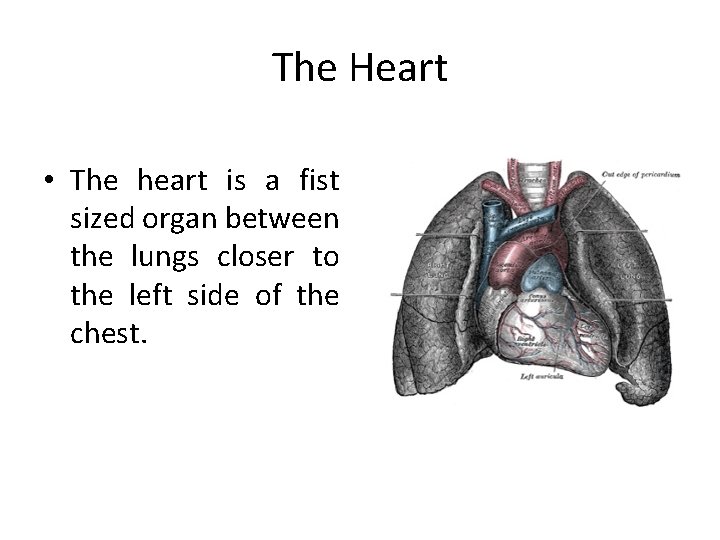

The Heart • The heart is a fist sized organ between the lungs closer to the left side of the chest.